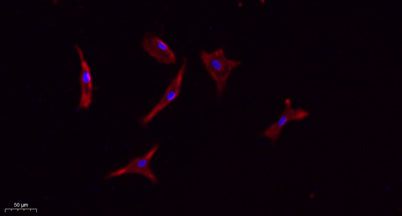

WB;IHC;IF;ELISA

Western Blot: 1/500 - 1/2000. IHC-p: 1:100-300 ELISA: 1/20000. IF 1:100-300 Not yet tested in other applications.

This gene encodes a pentaspan transmembrane glycoprotein. The protein localizes to membrane protrusions and is often expressed on adult stem cells, where it is thought to function in maintaining stem cell properties by suppressing differentiation. Mutations in this gene have been shown to result in retinitis pigmentosa and Stargardt disease. Expression of this gene is also associated with several types of cancer. This gene is expressed from at least five alternative promoters that are expressed in a tissue-dependent manner. Multiple transcript variants encoding different isoforms have been found for this gene. [provided by RefSeq, Mar 2009],